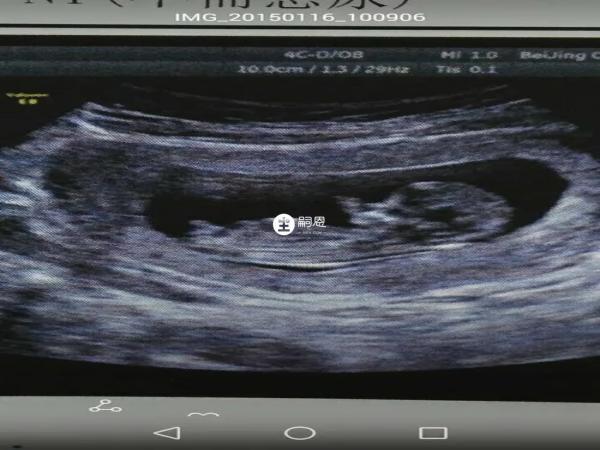

有寶媽分享已驗證生女孩的nt影象,其實nt看男女是非常準的一種方法,不過要想準確判斷,也需要具有專業知識才行,普通人一般很難分辨,或者醫院給出的nt單子可能並不是全景圖,會對胎兒性別特徵進行隱藏。另外,胎兒寶寶不同的體位,拍攝的角度,都會對判斷胎兒性別造成影響,需要多熟悉方法和技巧。

5、已生女兒nt檢查圖片